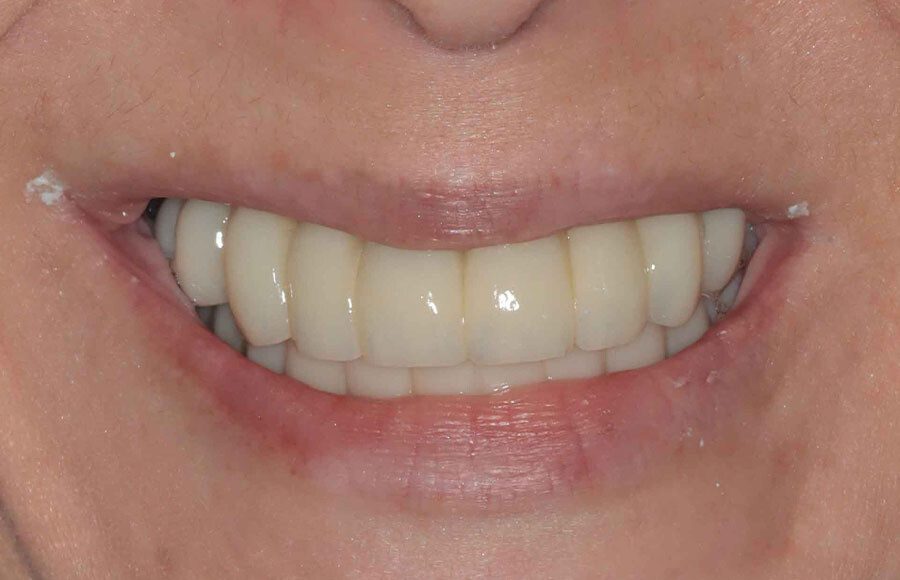

The patient couldn’t be happier with her new smile. We have improved not only her esthetics but her oral health as well. She now has beautiful restorations she can keep for years to come. Contact us if you would like to have a consultation and see if this is the right treatment for you!

The definitive bridges are delivered, the bite is verified, and the screws are torqued down firmly. The final result is strong, functional, and esthetic restorations that will serve the patient well for years to come.